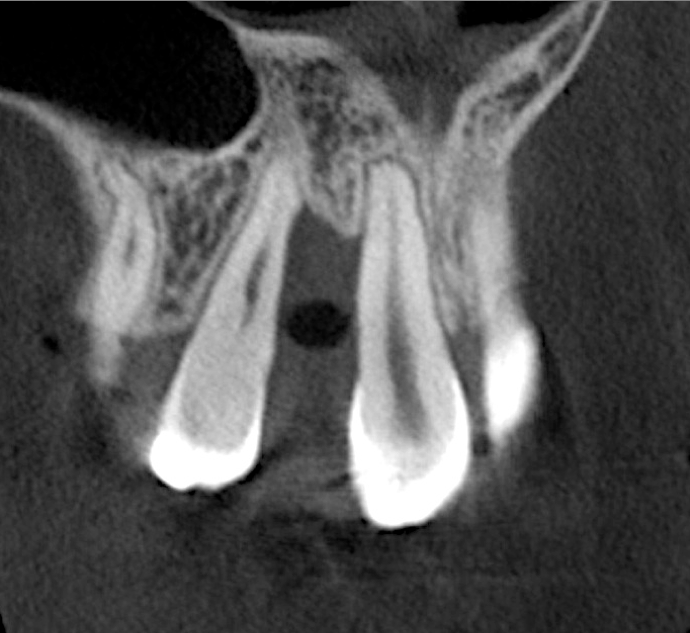

After 3 months of post-orthodontic stabilization, a cone-beam computed tomography scan was taken to re-evaluate the results and plan the future treatment sequence. Tomographic images clearly showed vertical gains in alveolar height, including in the edentulous area corresponding to tooth No. 7 (Figure 10 through Figure 12). The apex of tooth No. 8 was forced-erupted beyond its socket and could be visibly located within the soft tissue.30,33

Fig 10. Tomographic images of teeth Nos. 6 (Fig 10), 7 (Fig 11), and 8 (Fig 12) clearly showed vertical gains in alveolar height, including in the edentulous area corresponding to tooth No. 7. The apex of tooth No. 8 was located within the soft tissue because it was force-erupted beyond its socket.

Figure 10

Fig 11. Tomographic images of teeth Nos. 6 (Fig 10), 7 (Fig 11), and 8 (Fig 12) clearly showed vertical gains in alveolar height, including in the edentulous area corresponding to tooth No. 7. The apex of tooth No. 8 was located within the soft tissue because it was force-erupted beyond its socket.

Figure 11

Fig 12. Tomographic images of teeth Nos. 6 (Fig 10), 7 (Fig 11), and 8 (Fig 12) clearly showed vertical gains in alveolar height, including in the edentulous area corresponding to tooth No. 7. The apex of tooth No. 8 was located within the soft tissue because it was force-erupted beyond its socket.

Figure 12